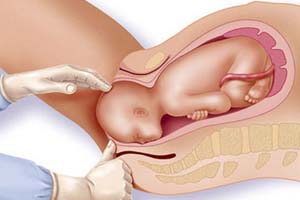

Best Maternity Hospital in Gandhi Path West, Jaipur

Delivering Hope, Health & Happiness